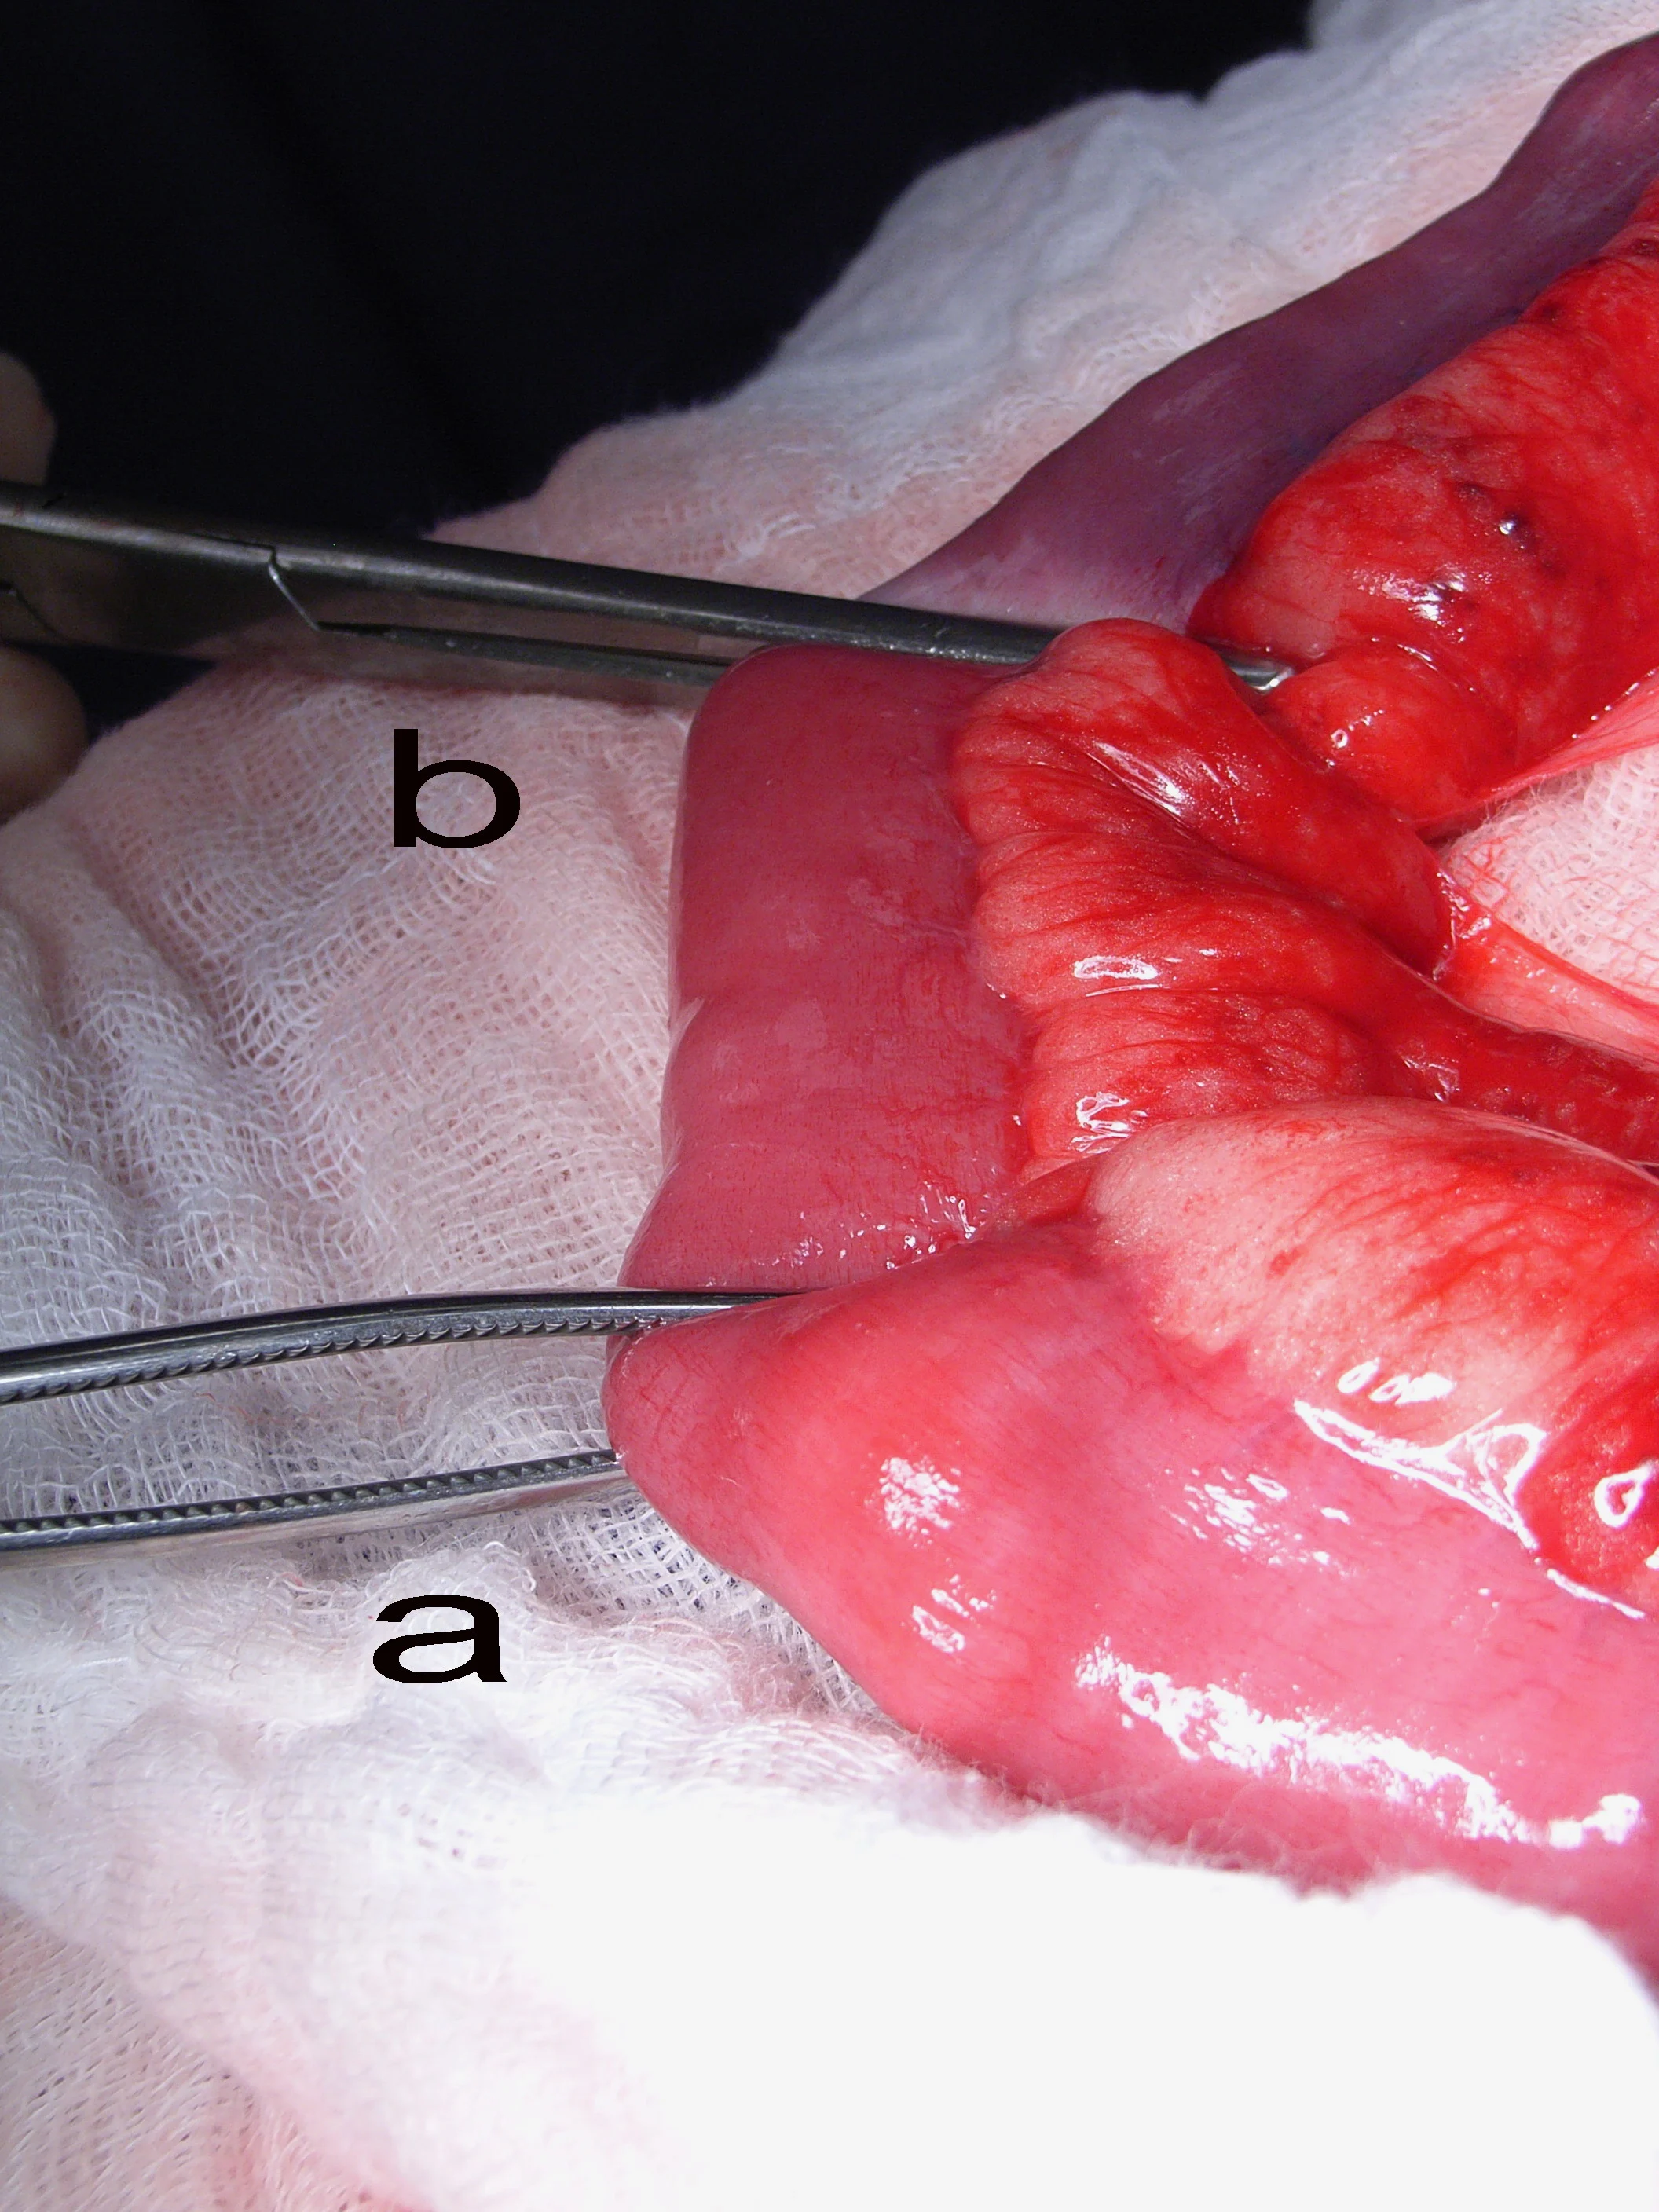

Author Insight

Crushing of the bowel ends can be minimized by grasping just the serosa of the bowel with the tips of the forceps. Note that the forceps on the left are handling the bowel by just grasping the serosa (correct), whereas the forceps on the right are grasping the full thickness of the bowel (incorrect).